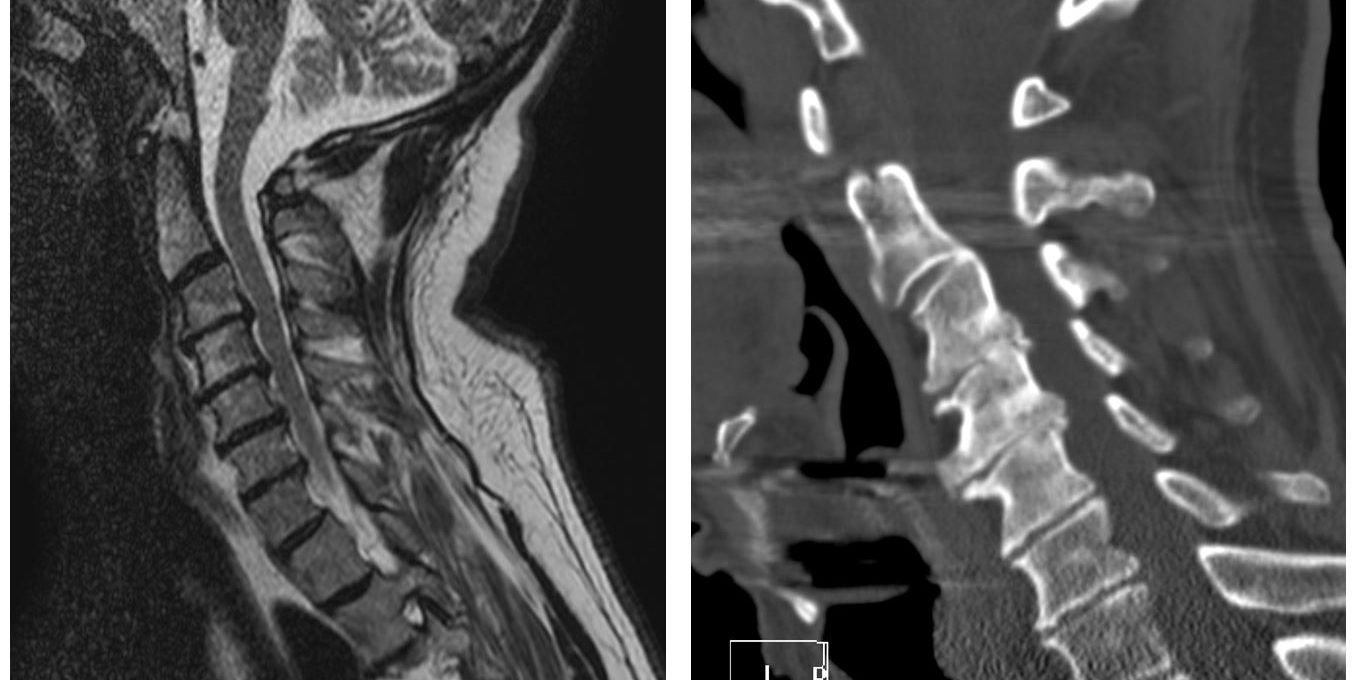

Αυχενική Δισκεκτομή σε 3 Επίπεδα